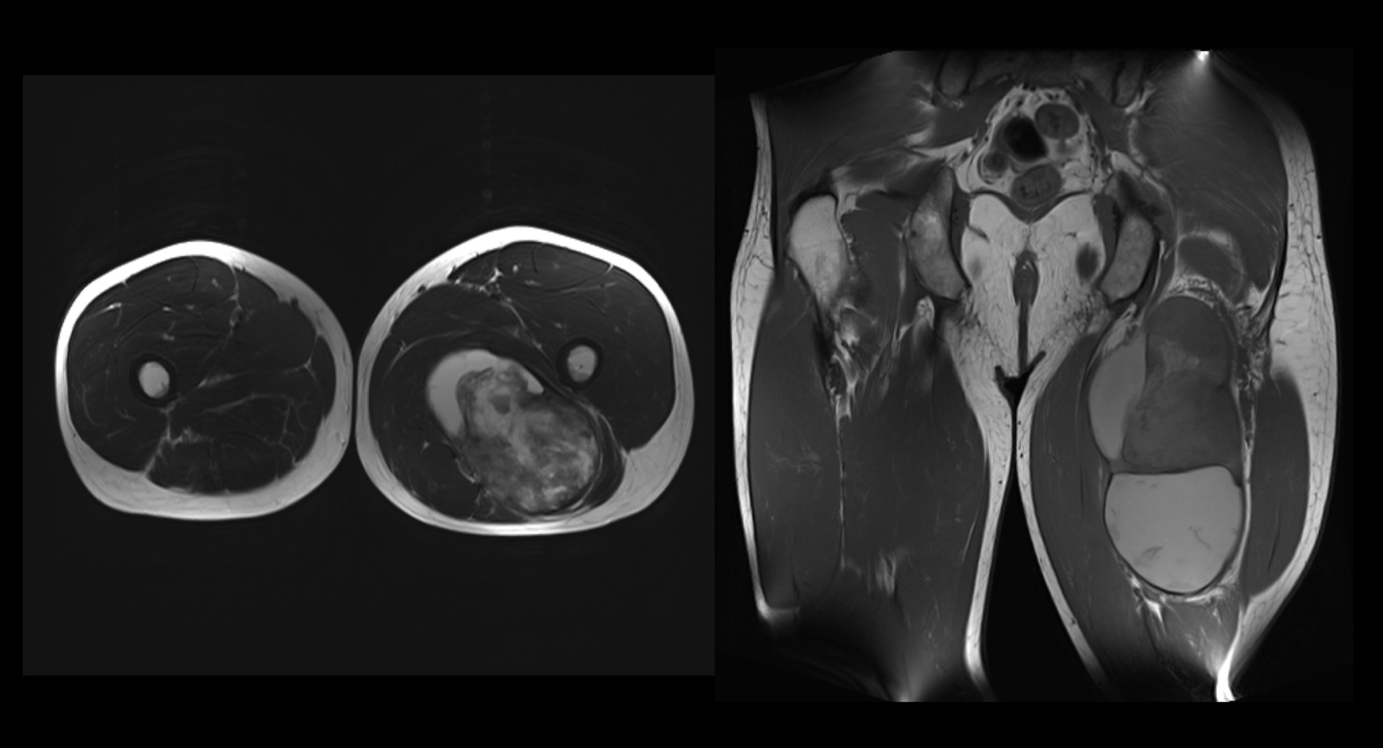

Schluckbeschwerden treten im hohen Alter relativ häufig auf. Sie können selbstlimitierend sein, aber auch länger anhalten. Bei länger bestehenden Beschwerden sollte eine Magenspiegelung durchgeführt werden. Ergibt sich daraus nichts, kann auch eine Breischluck-Untersuchung zielführend sein. Bei dem 65-jährigen Patienten (s. Abbildungen) handelt es sich beispielsweise um einen seltenen Befund: ein Zenker-Divertikel.

Bild 1: Hypopharyngo-Ösophagographie mit bariumhaltigem Kontrastmittel in sagittaler und coronaler Ansicht. Es zeigt sich eine dorsale Ausstülpung der hinteren Ösophaguswand auf Höhe von HWK5/6.